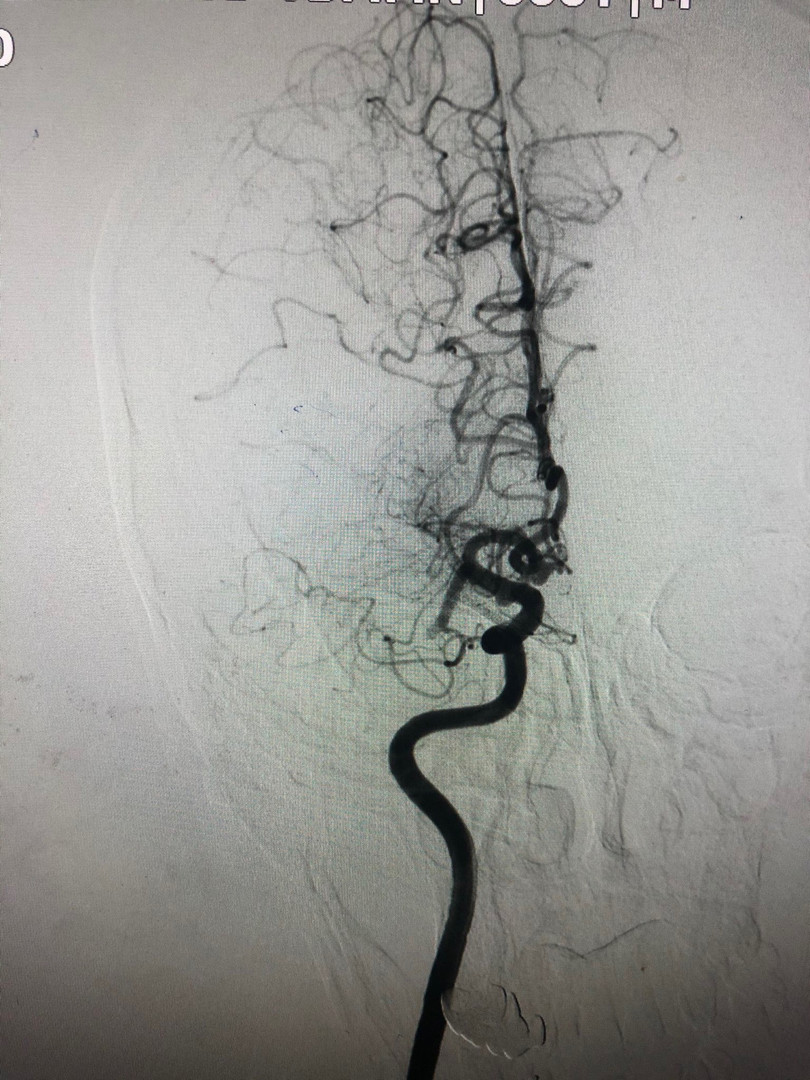

Sau khi tiếp nhận bệnh nhân, các bác sĩ đã chụp cắt lớp vi tính sọ não. Kết quả cho thấy bệnh nhân bị tắc động mạch não giữa bên phải. Ngay lập tức, người bệnh đã được can thiệp lấy huyết khối qua đường động mạch sau tai biến giờ thứ 6).

| Chụp tắc động mạch não giữa đoạn M1 phải. Ảnh: BVCC |